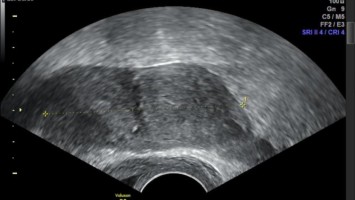

Alles weist auf eine Echinokokkose – doch das war es nicht

Die 29-jährige Patientin aus China stellt sich mit Appetitverlust und Druckgefühl im Abdomen vor. Obwohl sie weniger isst als zuvor, hat sie in den letzten Wochen 3 Kilo zugenommen. Der Ultraschall lässt schnell einen Verdacht für die Ursache ihrer Beschwerden aufkeimen: eine riesige polyzystische Raumforderung – typisch für eine Echinokokkose. Oder doch nicht? Eine englischsprachige Kasuistik.